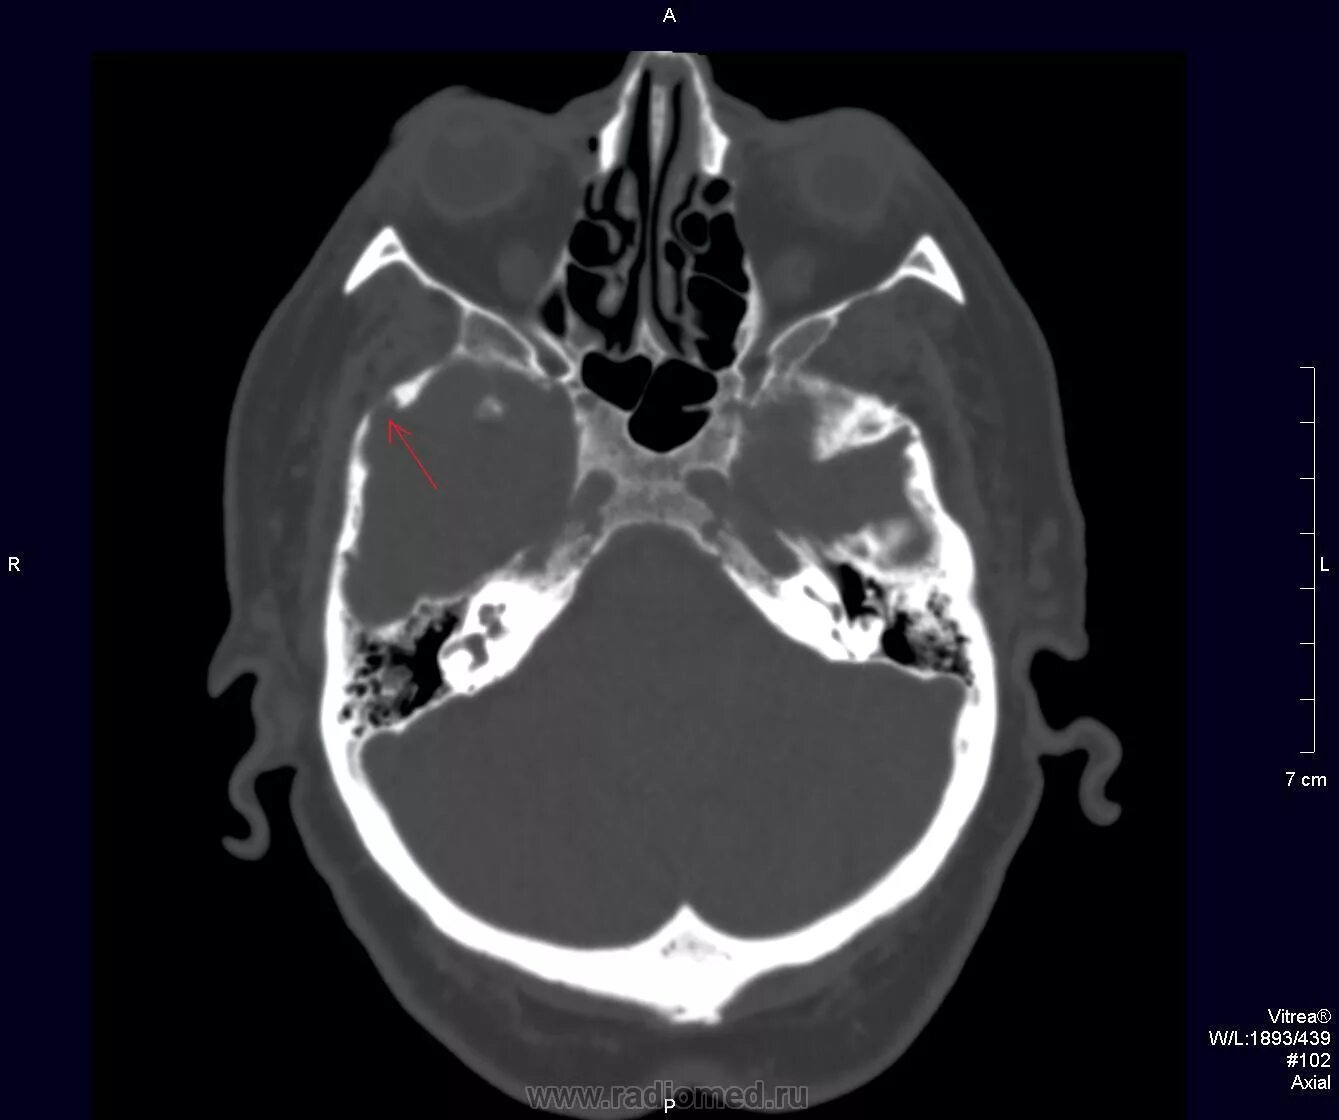

Череп на кт